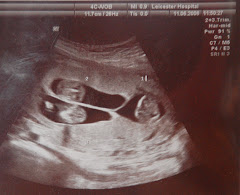

I will close with some more photos, unfortunately we could only get decent pictures of baby 2 at the private 'bonding' scan we went to last Saturday. Baby 1 was tucked right down in my pelvis (hence the pressure on Friday night) and Baby 3 ( a confirmed girl by the way) - wasn't in the mood to have her picture taken. I have had to explain to people that it's not that I'm having to come to terms with having two girls as oppose to two boys, that's easy to get my head around - what I'm struggling to get to grips with is the fact that I was wrong - still can't quite believe that - how can that be? me? wrong? - no - it just doesn't make sense!!

It's weird how these pictures come out really - TFK said they remind him of the melting metal of ' The Terminator' - I know what he means but now I can't look at them without thinking of that last scene in T2 when the Terminator police man just keeps changing shape and coming back to try and kill Arnie. Thats not what you should be thinking about when youre looking at pictures of your unborn. Bloody good movie though.

'No more pictures please'

'I'm melting - I'm melting' - cute face though

When you are expecting triplets you have no end of scans- The picture above shows baby 2 and 3 at 12 weeks in what looks like little bunk beds. Baby 3 is lying under the bed somewhere!!

Baby 2 likes having her photo taken, but then she seems to always have the best seat in the house. This is her at 19 weeks.

Poor baby 1, the boy, is in a slightly less comfy position, you can just see his little feet crossed over and sticking out from his sleeping bag, the other two kind of sit on top of him - poor lad.

This is a rare picture of the illusive baby 3 - the most tricky one to photo - but making him/herself known more recently, by kicking me in the ribs mostly. This is him/her resting hand on chin at 24 weeks.

We were amazed by this picture. It is baby 2 waving at the camera like a superstar at 24 weeks - even at such a tender age she seems to resemble her older brother Eli.